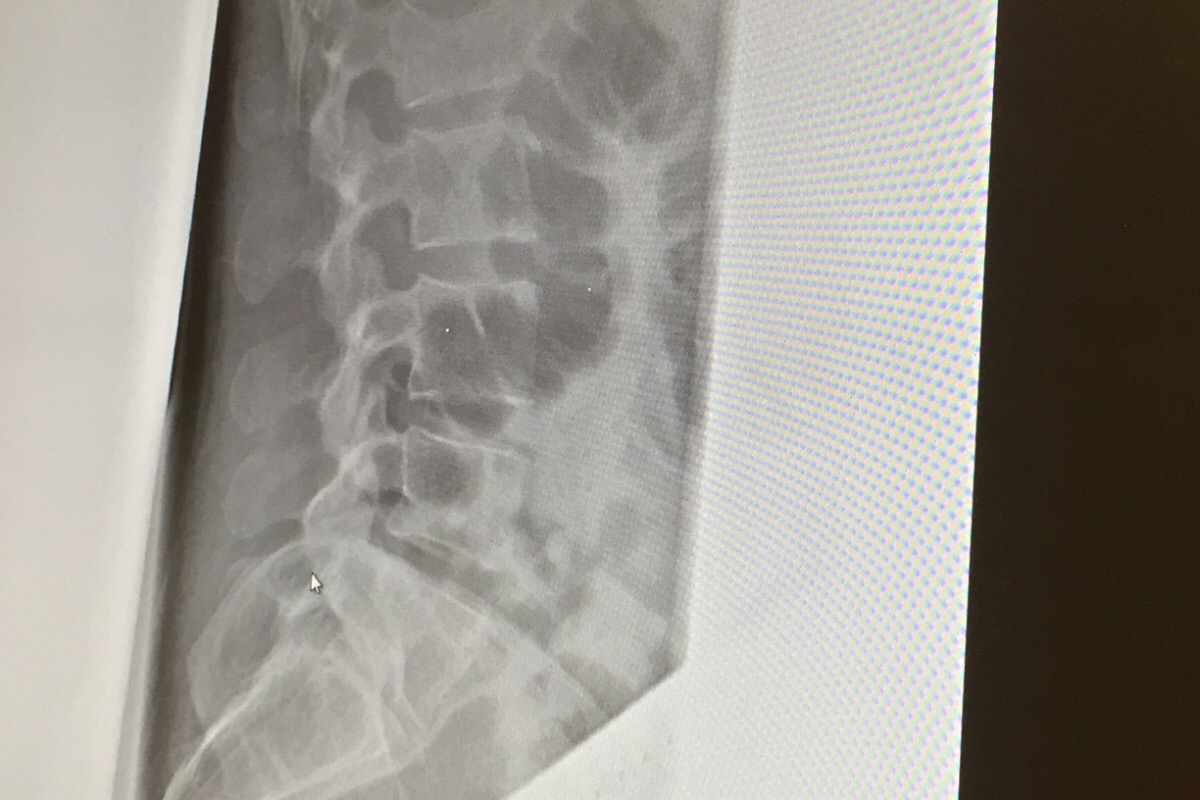

I got hit by a car while riding my bike to work on Monday. I missed all this week and am not allowed to return to work until the end of next week. The picture is my fractured L1 vertebra. It’s the worst pain I’ve ever felt in my life and without insurense  I could really use your help and generosity so I can pay for medical bills while I working on taking legal action. Any little bit helps. Thank you so much for reading.